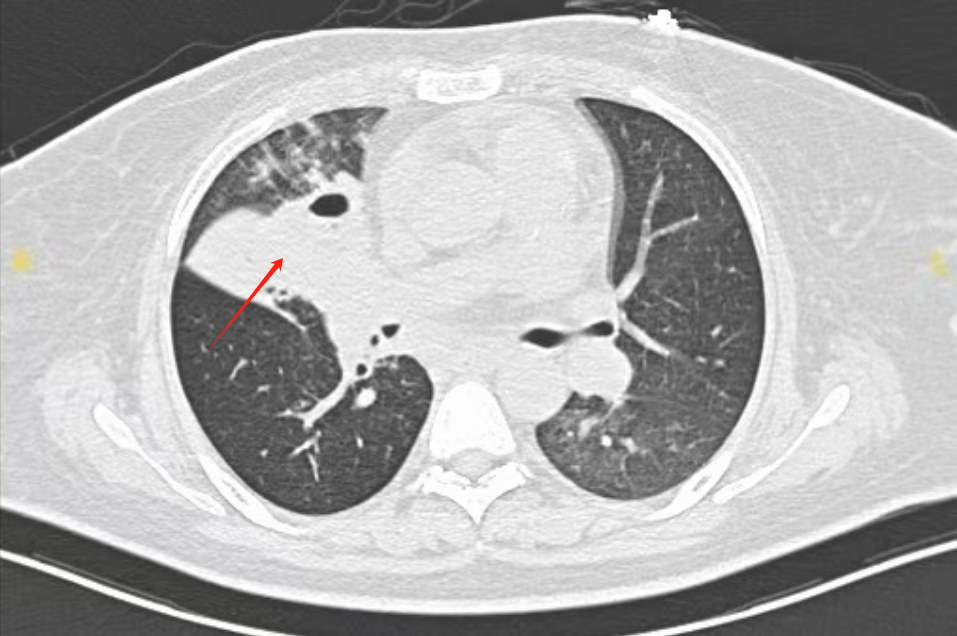

患者右肺呈现大片白色

来自河北的唐女士怎么也没想到,一场看似普通的咳嗽,竟让她在鬼门关前走了一遭。4个月前,她因咳嗽、胸闷,先输了10天消炎药,症状没好转反倒加重了,出现呼吸衰竭被紧急送到市级医院,气管插管后送进ICU。CT扫描让人倒吸一口凉气:右肺被大片白色阴影笼罩。而气管镜下可见右主支气管被“毛霉菌团”完全堵死——这意味着,她的肺正在“发霉长毛”!